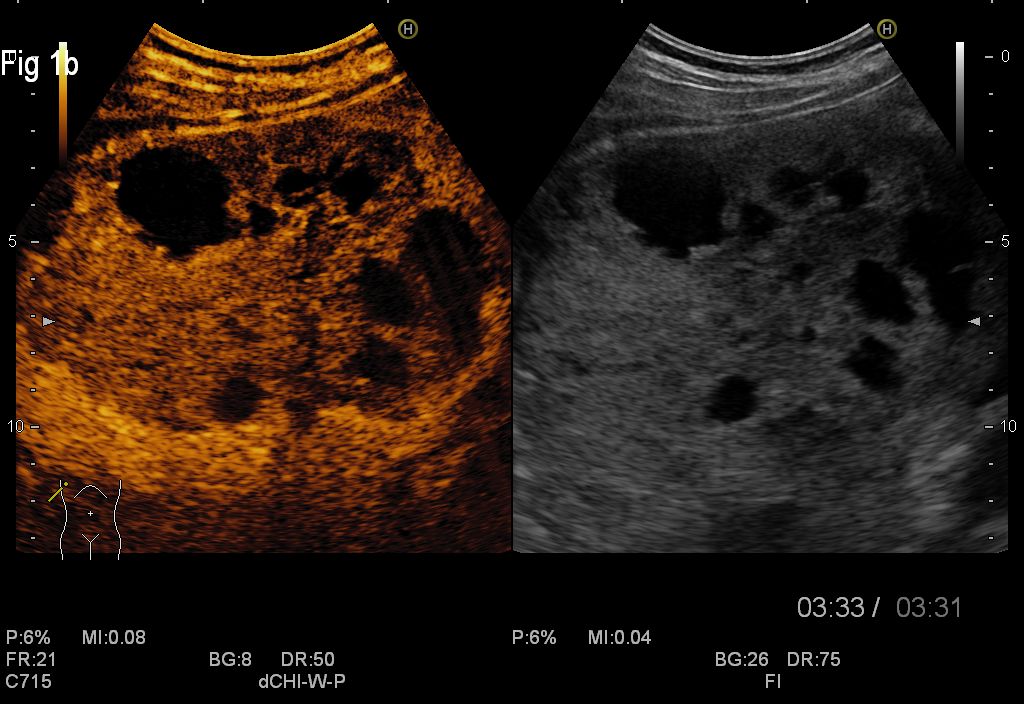

Figure 1a,1b. CEUS of the secondary cystic liver masses in the late venous phase

For this case, CEUS supported the diagnosis of cystic metastases, whilst studies showed previously that CEUS represents a useful method in clinical practice and clearly improves the differential diagnosis between malignant and benign liver lesions detected on standard ultrasonography, with a positive predictive value of 95.4% and negative predictive value of 95.9%. The main criteria for malignancy on CEUS is contrast wash-out in the late portal venous phase whereas benign lessons typically remain iso-enhancing with the surrounding normal liver tissue (5,6). Metastases usually show a brief arterial hypervascularity and complete rapid wash-out, which can improve detection during the portal phase (7). Neoplastic cysts such as cystic metastasis can be characterized on CEUS by sensitive real-time demonstration of vascular flow within the septa or solid component. Non-neoplastic complex cysts such as hemorrhagic cysts or hydatid cysts show the absence of intralesional enhancement on CEUS, thus confirming their non-neoplastic nature (8).